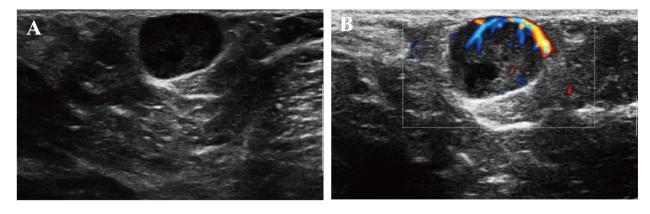

彩色多普勒超声(彩超):右侧腋窝皮下见一混合回声结节,大小约13 mm×10 mm,形状呈椭圆形,边界清,结节内部以低回声为主,可见片状无回声区,后方回声增强(图1A);彩色多普勒血流显像(CDFI):结节周边见条状血流信号,结节内血流Adler分级为Ⅲ级血流(图1B),并可探及动脉频谱,收缩期峰值速度(PSV)4.71 cm/s,血管阻力指数(RI)0.43;双侧乳腺及左侧腋窝区未见明显异常回声,考虑右侧腋窝皮下表皮样囊肿并感染可能。乳腺钼靶:双乳呈透亮脂肪型,乳晕后区可见少许条索状、类结节状致密阴影,双乳未见明显肿块;双乳晕、乳头和皮肤未见异常;右腋下见一稍大淋巴结影,大小约12 mm×11 mm,左腋下未见肿大淋巴结影(钼靶检查对乳腺肿物观察有一定的优势,但由于视野受限,无法充分暴露腋窝区,故对腋窝区病变观察有一定的局限性。此次钼靶检查未发现右侧腋窝肿物,有可能是由于肿物位置靠后、超出检查仪器识别区域的原因)。初步诊断:①双乳呈脂肪型,增生改变;②右腋下淋巴结反应性增生。

图1 一例副乳腺包裹性乳头状癌合并乳腺癌患者右侧腋窝区彩超图

注:A 为超声二维图像,右侧腋窝皮下见一混合回声结节,形状呈椭圆形、边界清,结节内部以低回声为主,后方回声增强、内壁光滑;B 为CDFI图像,结节内部可探及丰富血流信号。